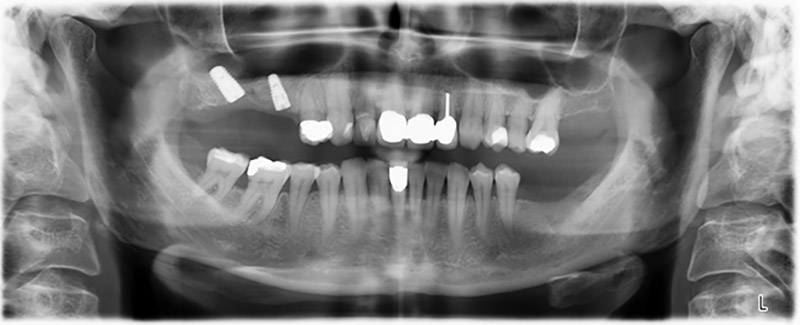

Die 59-jährige Patientin wurde mit einer fortgeschrittenen Parodontitis vorstellig, beschrieb ein ungutes Gefühl und einen schlechten Geschmack ausgehend vom ersten Quadranten distal. Die klinische Untersuchung zeigte allgemein erhöhte Taschentiefen und einen stark fortgeschrittenen Knochenabbau in regio 16 und 14. Die radiologische Untersuchung untermauerte den Befund (Abb. 1). Die Zähne 16 und 14 waren nicht zu erhalten.

Etwa sechs Monate nach Extraktion der Zähne 16 und 14 wurde zur Planung und Risikominimierung eine digitale Volumentomografie (DVT, Planmeca) erstellt. Hierbei wurde deutlich, dass der Knochen sich nicht in der gewünschten Quantität regeneriert hat (Abb. 2 bis 7).